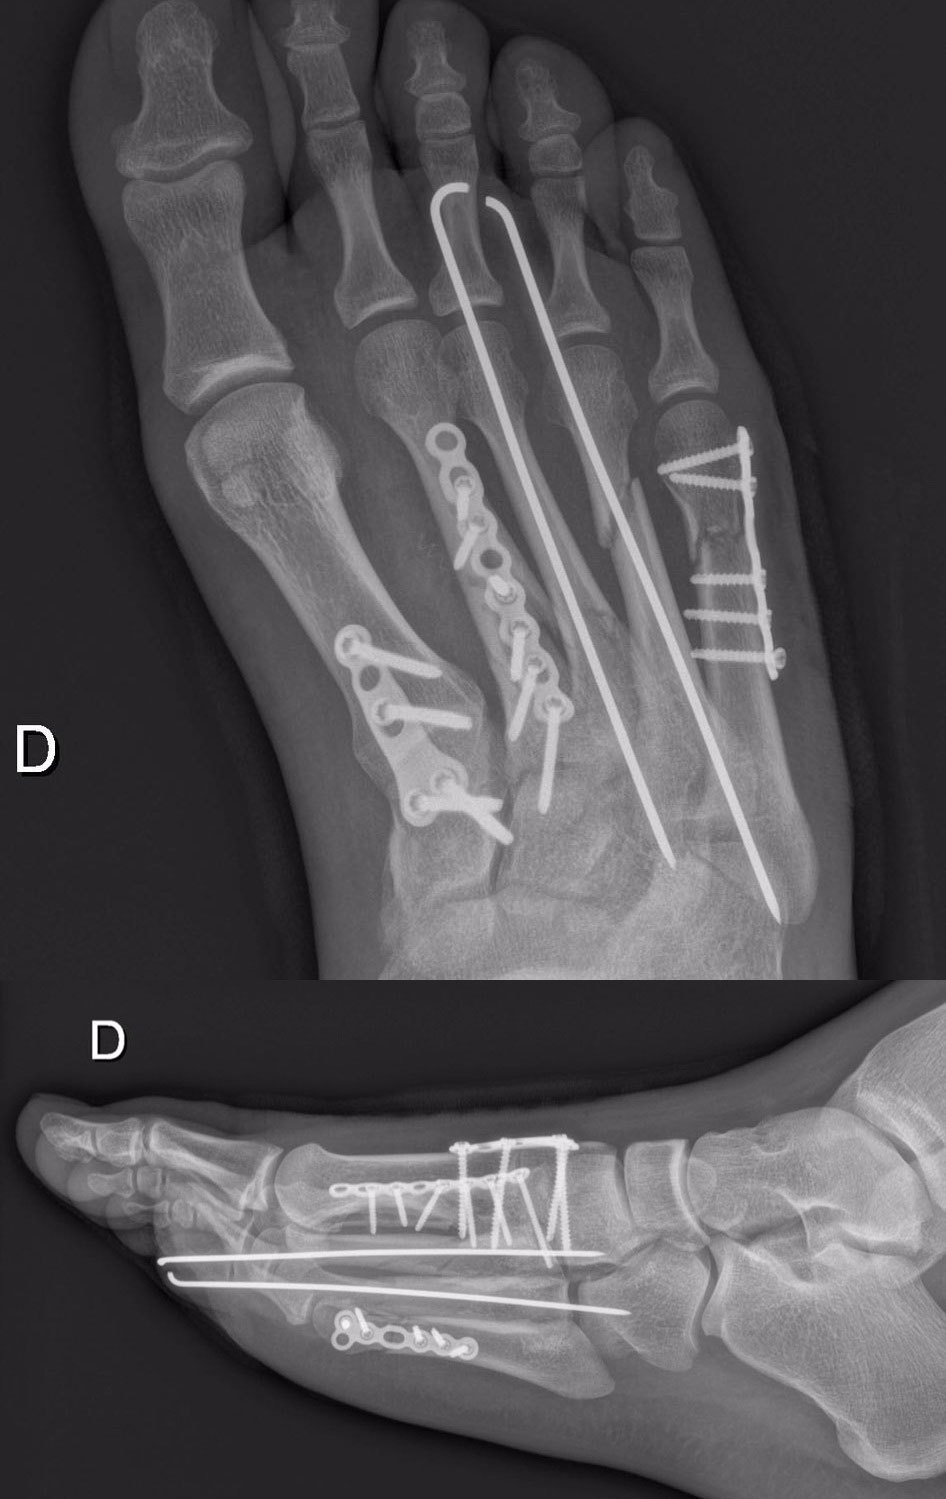

Sementara Miller dan Bautista lolos dari cedera, kaki kanan Baz mengalami beberapa patah tulang metatarsal. Pada hari Kamis (26/5), Baz pun menjalani operasi di Hospital La Tour Meyrin, Jenewa, Swiss selama 1,5 jam untuk menanamkan dua tusuk titanium, tiga plat dan 15 skrup.

Kaki kanan Loris Baz pascaoperasi di Swiss. (c) Avintia Racing

Pebalap Prancis berusia 23 tahun ini diperkirakan membutuhkan waktu selama 4-6 pekan untuk pulih, yang berarti ia harus absen dari Seri Catalunya dan uji coba pascabalap. Meski begitu Baz menargetkan untuk kembali di MotoGP Belanda yang digelar di Sirkuit Assen pada 24-26 Juni mendatang.